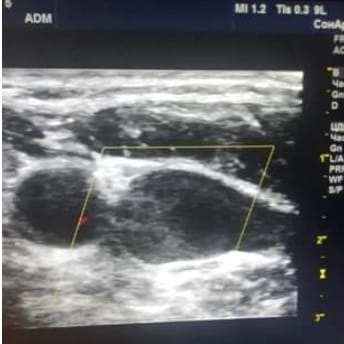

Бүгін қалқанша безді Ультрадыбыстық әдіспен қарап отырып "кездейсоқ табу" болды.Өте қауыпты , себебі ми қан тамырларына қан дұрыс бармай, кез келгенде тромб болуы мүмкін.